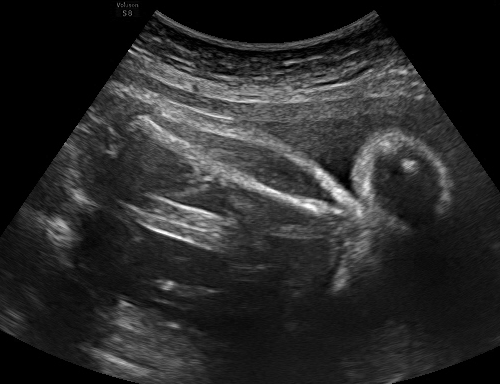

TABLE I: Sample outputs comparing reference captions with captions generated by the proposed model.

Uterine Ultrasound Image Reference Caption Generated Caption

[Uncaptioned image] a white straight line at the top center that represents the femur bone it is possible to calculate the femur length the knee is straight a white line at the top center that represents the femur bone it is possible to calculate the femur length the knee is straight

[Uncaptioned image] a large slightly oval circle that represents the cranial contour of the fetus inside it is possible to see the cavum of the septum pellucidum on the right only but it is possible to calculate the biparietal diameter a large slightly oval circle that represents the cranial contour of the fetus the cavum of the septum pellucidum can be seen on the right it is possible to calculate the biparietal diameter

Consequently, the CNN-BiGRU model outperformed the other baseline models regarding BLEU and ROUGE scores and demonstrated lower loss values, underscoring its effectiveness in this application. Moreover, Table I provides further evidence by illustrating sample outputs that compare reference captions with captions generated by the CNN-BiGRU model. This comparison vividly showcases the model’s ability to generate high-quality captions through its robust bidirectional processing capabilities.